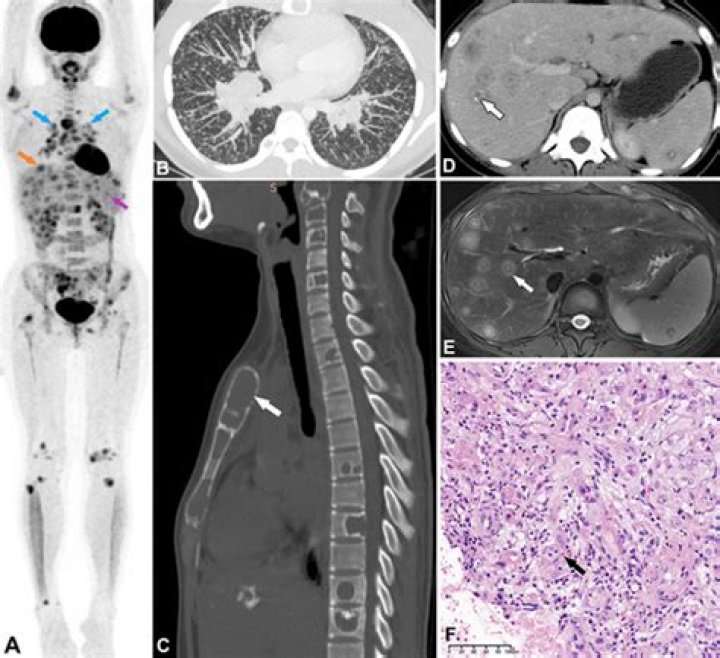

Epithelioid hemangioendothelioma, or EHE, is a rare cancer that grows from the cells that make up the blood vessels. This cancer can occur anywhere in the body with the most common sites being the liver, lungs, and bone.

Epithelioid hemangioendothelioma, or EHE, is a rare cancer that grows from the cells that make up the blood vessels. This cancer can occur anywhere in the body with the most common sites being the liver, lungs, and bone. It usually happens in people between 30 and 50 years of age but can also occur in young children and older people.

Which lung CT findings are characteristic of pulmonary epithelioid hemangioendothelioma?

Conclusions: Multiple small nodules pattern was the most common findings of pulmonary epithelioid hemangioendothelioma. Patients with pulmonary epithelioid hemangioendothelioma have good prognosis. Keywords: CT; clinical course; epithelioid hemangioendothelioma; lung.